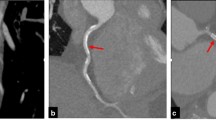

A relatively novel advancement in cardiac CT imaging is use of delayed enhancement to detect myocardial scar within a viability assessment. The practice uses the similar kinetic properties shared by iodinated contrast agents in CT and the gadolinium agents of CMR (where delayed enhancement is classically employed), resulting in comparable myocardial characterisation between modalities [49]. For CMR, quantitative late gadolinium enhancement is established as a potent tool to risk-stratify hypertrophic cardiomyopathy patients, given its prognostic value in predicting sudden cardiac death [50]. The presence of late gadolinium enhancement on CMR predicts all-cause mortality, ventricular arrhythmia, sudden cardiac death, cardiovascular mortality and major adverse cardiovascular events, independent of LVEF in both ischaemic and non-ischaemic cardiomyopathy [51, 52]. In the evaluation of the myocardium post-infarction, animal studies have shown that CT utilising delayed enhancement is a valid imaging modality [53, 54]. Whilst delayed enhancement in CT has some promise, the equivalent phenomenon in CMR is known to have superior resolution and less difficulties in patients with respiratory pathology [49]. In addition, > 18 g of myocardial fibrosis (as assessed by CT) is associated with increased risk of spontaneous ventricular arrhythmias resulting in ICD activation for patients with hypertrophic cardiomyopathy [55]. This opens the possibility of risk-stratifying HF patients who would benefit from implantable defibrillator. Hence, whilst delayed enhancement in CMR is currently (and rightfully so) used over CT, the current promise shown by the latter warrants its consideration in the context of CMR being contra-indicated, as well as supports the notion that future research is needed in the area.